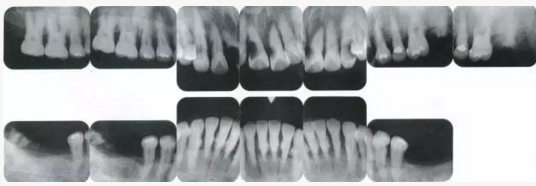

2222222222.png

▲圖19-1

40歲,女性。來院主訴為牙齦出血,牙體晃動?;颊卟晃鼰?,因此沒有全身性問題。有明顯的牙周炎,發(fā)生了牙體移動,前牙區(qū)前突。下頜右側(cè)磨牙缺失,醫(yī)生認為有必要進行包括牙周修復(fù)、正畸治療、種植治療等在內(nèi)的綜合性治療。

22222222222222.png

▲圖19-2,3

上下頜咬合面照。

22222222222222222222222222.png

▲圖19-4

X光片。牙槽骨明顯缺失。